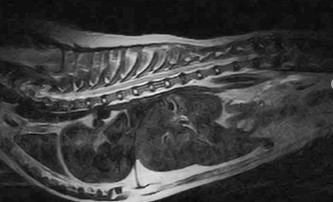

W obrębie kanału kręgowego najczęstszymi wskazaniami do badania rezonansem magnetycznym u zwierząt są:

• ocena przepukliny i stopnia ucisku na rdzeń kręgowy

• dyskopatie, neuropatie, radikulopatie

• urazy kręgosłupa